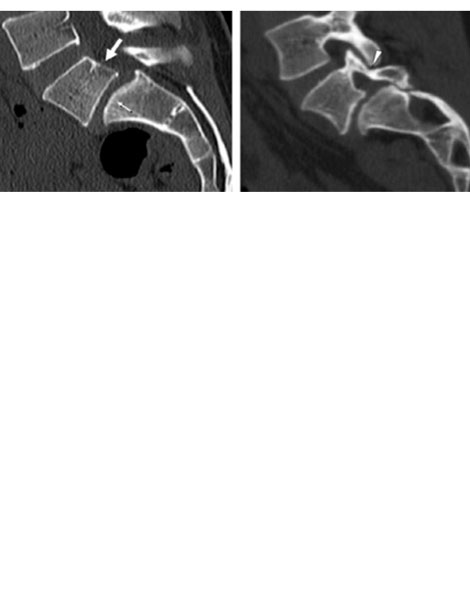

DIAGNOSTICO:

Estudios Radiográficos: